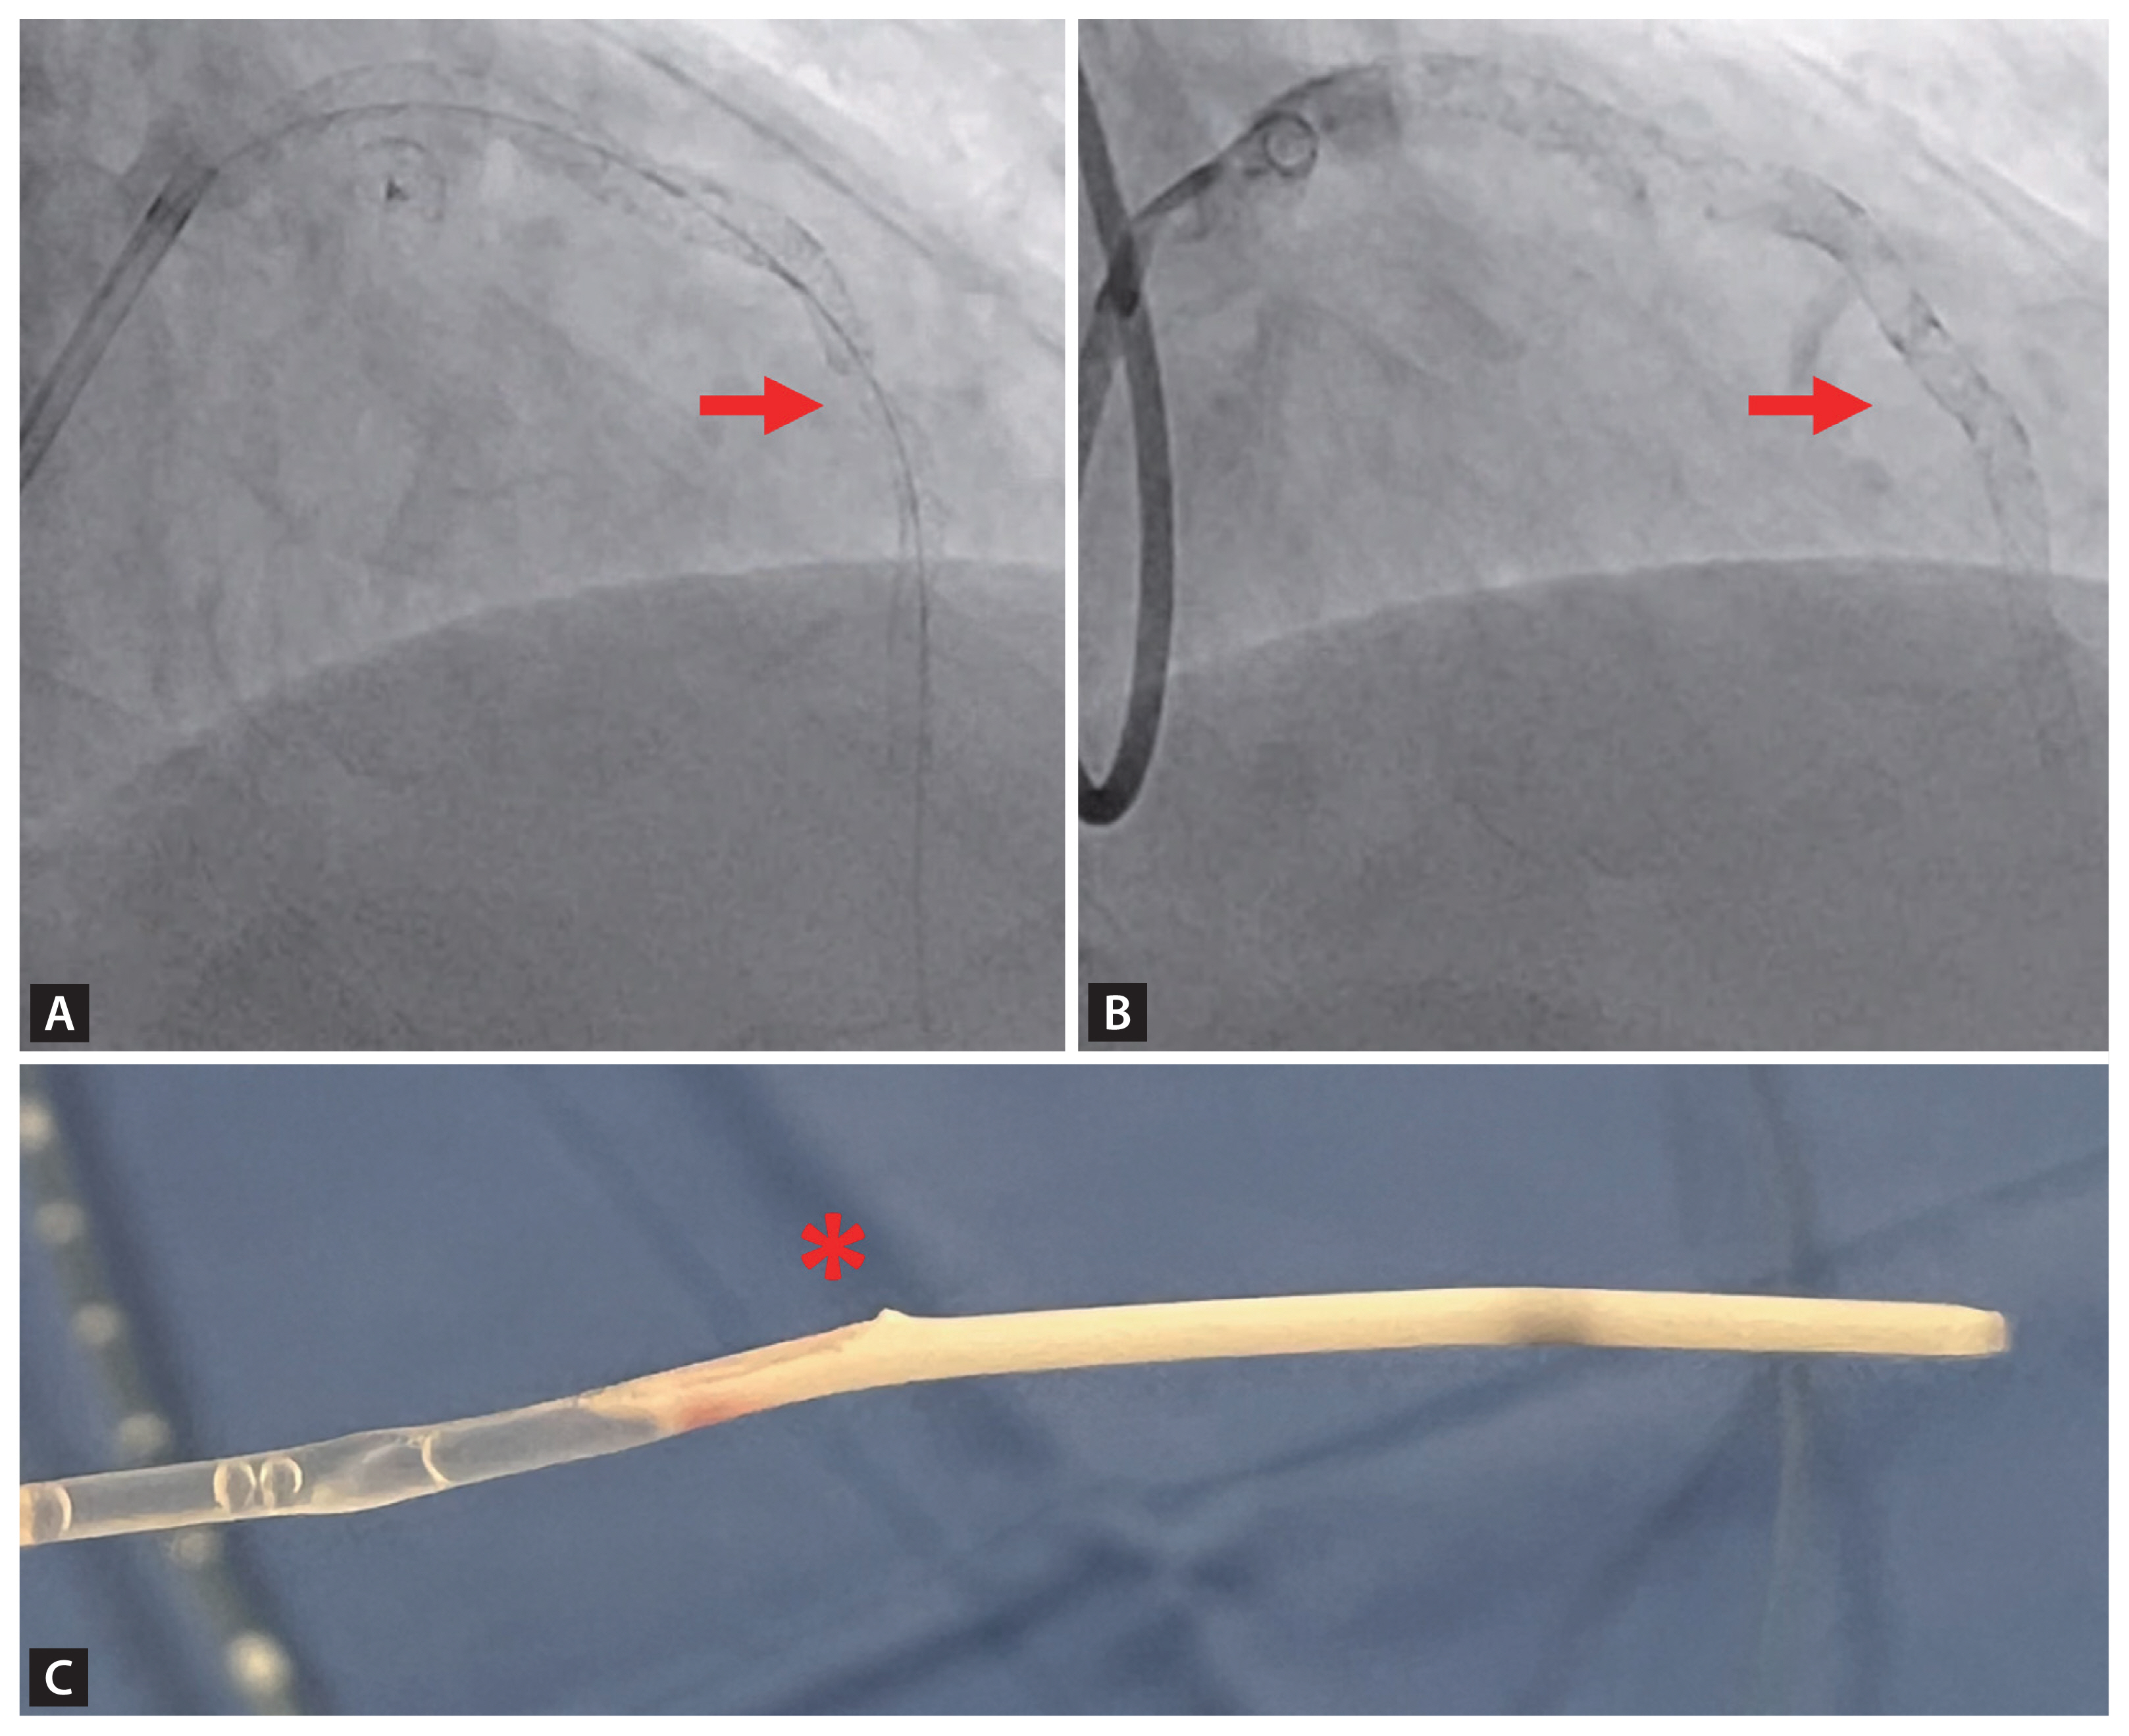

Too much synchrony? Left bundle branch area pacing-induced systolic anterior motion and left ventricular outflow tract obstruction managed by intentional atrioventricular dyssynchrony

- Hyung Ki Jeong, Sung Soo Kim, Hyun Kuk Kim, et al.

-

Korean J Intern Med. 2026;41(2):367-368.

Image of interest

March 1, 2026